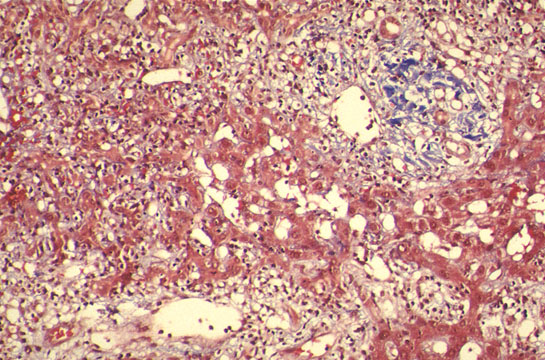

"Lobular disarray"

Fig 97 - "Lobular disarray": Loss of hepatocyte, inflammatory reaction, Kupffer cell mobilization an hepatocellular swelling distort the pattern of the liver plates somewhat confusing the lobular architecture.(H&E stain).